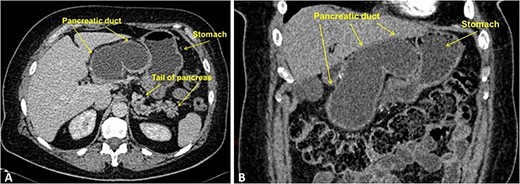

CT scan demonstrated enormous cystic dilatation of the MPD up to 75 mm with total atrophy of the pancreatic head and body parenchyma with dilatation of the branch ducts in the tail up to 6 mm (Fig. 1).

Contrast-enhanced CT, portal-venous phase: (A) axial; (B) frontal. The images demonstrate marked smooth cystic dilation of the head and neck region of the pancreas with duct dilation into the body (arrowheads), without mural nodules or side branch dilatation.